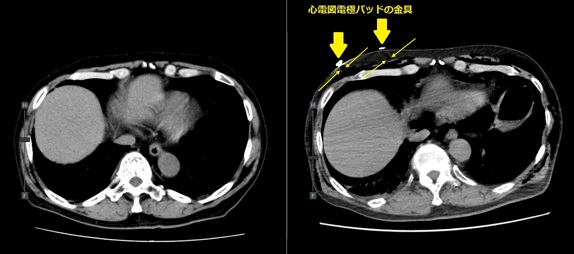

図2. 心電図電極パッドによりアーチファクトが写り込んでいるCT画像の例

金属類の周りに黒い帯状の筋のように見えるものが金属アーチファクトです。図2では黄色い矢印で挟まれた部分(→ ←)に現れています。